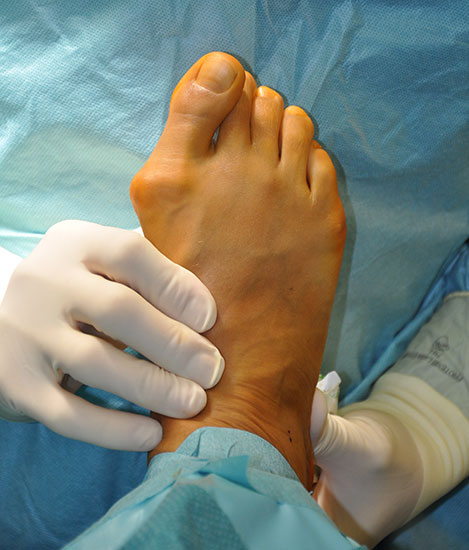

Abschließend erfolgt die klinische Kontrolle hinsichtlich Stellung, Alignement und passiver Funktion. Überprüfen der Sehnenspannung durch den retrocapitalen Push-up Test.

Postoperativ ist auf eine Zügelung der operierten Zehen nach plantar zu achten, damit es in der Heilungsphase zu einer entsprechenden Position der Langzehen kommt. Dadurch kann einer Kontraktur der dorsalen Weichteile der betroffenen Zehen, inklusive Verkürzung der Strecksehnen vorgebeugt werden 12. Ein Vorfußverband in der Vainio-Technik mit dieser Zügeltechnik hat sich hier bewährt.